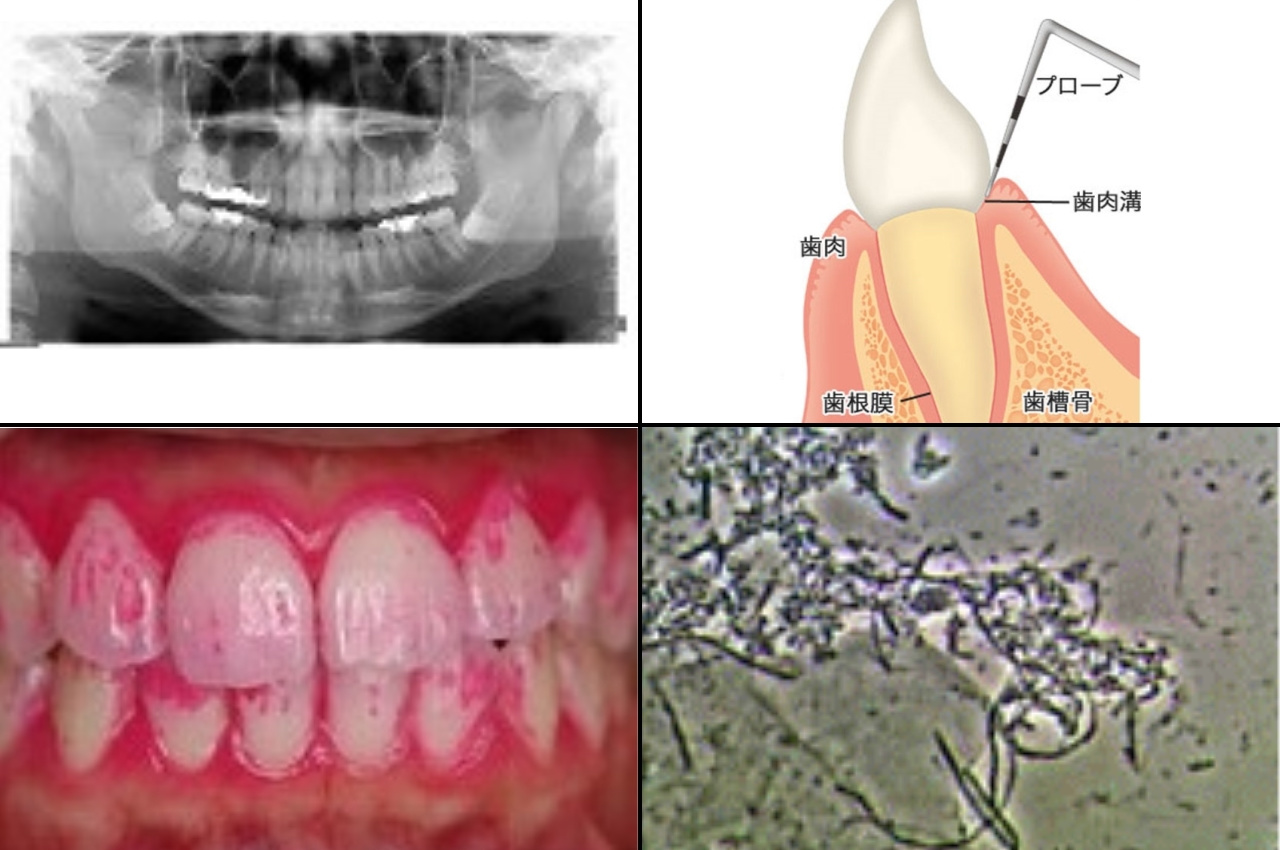

歯周病の原因と進行 山形県東根市の歯医者 森歯科クリニック

歯周病の原因 歯茎から血が出る 港区浜松町 大西歯科モノレールビルクリニック

歯周病とは 小林歯科医院 野洲市 小篠原の歯医者 歯科

お口の健康について 西歯科クリニックから歯周病と口腔乾燥症のご案内